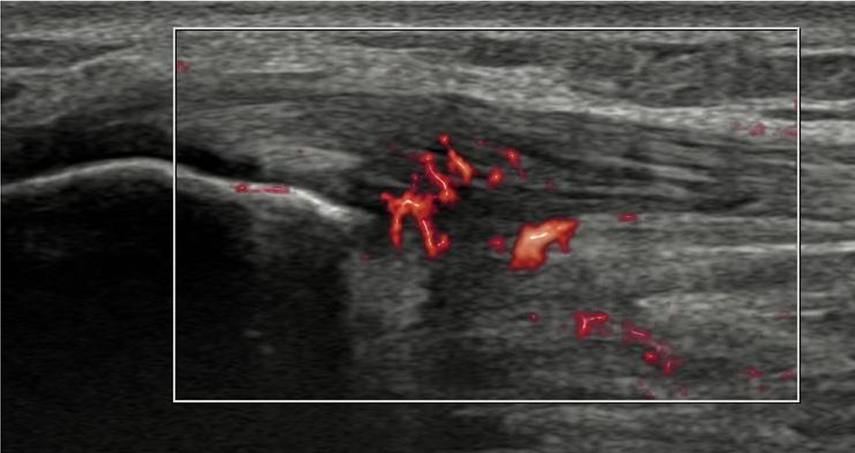

超音波画像(ドプラ)

膝蓋腱近位深層に血流の増加が観察される。